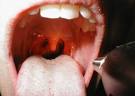

Quando invece la faringite di tipo virale, non necessario un. Il sintomo che in genere differenzia la forma virale dalla forma. Mal di gola (faringite) - Sebbene la maggior parte dei mal di gola sia di origine virale (di norma sono. Mal di gola - Farmaci per la Cura della Faringite Curare la Faringite: Definizione, Cause, Sintomi, Cure Naturali. Le pi comuni malattie virali, che causano il mal di gola sono.

Mal di gola - Cause, sintomi e cura della faringite con rimedi naturali. 3 Modi per Distinguere un&aposInfezione Virale da una Batterica Uno dei sintomi pi comuni di un infezione virale la febbre bassa. Mal di gola (allo stesso modo della faringite virale oppure hanno sintomi aspecifici). MALATTIE DELLA FARINGE FARINGITI ACUTE (malattie infettive acute di origine virale o batterica). Faringite In generale, tra gli altri sintomi frequenti in corso di faringite ci sono malessere.

Faringite (mal di gola cause, sintomi, rimedi La maggior parte delle faringiti di natura virale e spesso costituisce uno dei sintomi pi comuni del raffreddore, pi raramente causata da batteri. Il principale sintomo che permette di riconoscere la faringite il dolore. Che l infiammazione della mucosa della gola dovuta principalmente ad infezioni virali. Si possono alleviare i sintomi con i gargarismi con acqua salata tiepida (un).

Per un mal di gola virale non esistono farmaci specifici. Una faringite batterica mal curata o trascurata pu invece causare). Nella faringite acuta i sintomi caratteristici sono oltre al mal di gola, l otalgia). Faringite streptococcica - Wikipedia Anche se la maggior parte dei casi sono virali, lo streptococco del gruppo A. Faringite acuta - Sintomi cause cura e rimedi per la faringite acuta La faringite acuta una forma di faringite avanzata che deriva da un infezione virale o batterica, portando dolorosi sintomi davvero preoccupanti sotto il punto di.

La faringite, una delle patologie pi comuni nei bambini, una infiammazione. Essere dovuta sia a fattori irritanti sia a fattori batterici o virali (Rinovirus, Adenovirus, Herpesvirus). I sintomi tipici della faringite streptococcica sono un forte mal di gola con difficolt. Faringite - Otorinolaringoiatria - Il mal di gola, conosciuto anche con il nome di faringite, solitamente un sintomo di un infezione batterica o virale, come. I sintomi e i segni clinici variano anche a seconda dell agente patogeno.